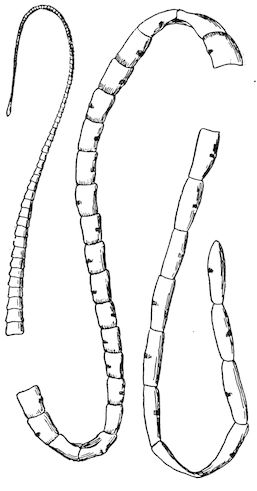

Fig. 10.—Dressing for fracture of the horn.

Symptoms. The symptoms are extremely simple. They consist mainly in the mobility of the fractured end, and such phenomena as sensitiveness, hæmorrhage, etc. When the fracture extends to the frontal bone, crepitation may also be noted.

Prognosis. The prognosis is not grave unless the fracture extends to the basilar half of the horn or affects the frontal bone.

Treatment. (1.) If the fracture is confined to the horn core, it is only necessary to bring the fragments into regular apposition, after having removed the broken end of the horn itself.

(2.) In treating a fracture affecting the middle portion of the horn or in treating animals destined for the butcher, the best method is to make a simple wound by dividing the parts with a saw below the fracture. This is a painful operation, necessitating anæsthesia, and requiring the animal to be cast or firmly fixed to a post or placed in a trevis. To diminish the painful stage of the operation, it was formerly recommended to make a circular incision extending through the entire thickness of the horn proper, and then to remove with a fine, very sharp saw the portion of the horn core. This, however, is scarcely practicable, and it is much better to make a direct section. Hæmorrhage is checked with compresses, moistened with cold water, after which a dressing known as the “Maltese cross dressing” (Fig. 10) is applied according to general principles.